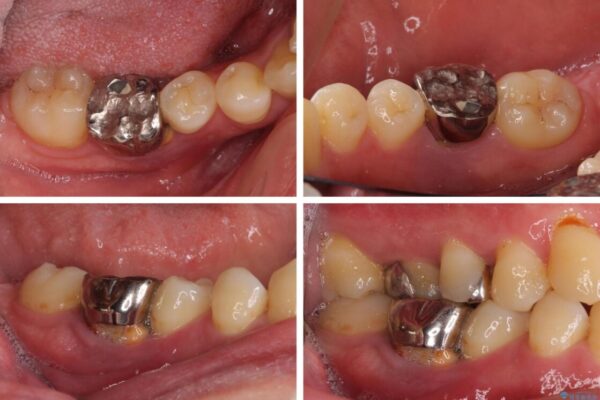

左右下顎の大臼歯は、ともに歯根が破折しており、抜歯が必要な状態でした。

放置したことで炎症による骨吸収が顕著であるため、骨造成を併用してインプラント埋入を行うこととしました。

矯正治療でインプラント埋入を行い、矯正治療後に気になる前歯と合わせてオールセラミッククラウンによる補綴治療を行うこととしました。

治療途中

• 割れてしまった奥歯とデコボコの前歯 矯正治療とインプラント治療 治療途中画像